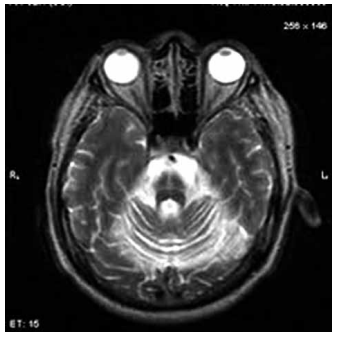

Homem de 45 anos foi atendido na emergência após

sofrer uma queda de altura. A tomografia de crânio encontra-se a seguir.

Com base nesses achados, qual é o diagnóstico mais provável?